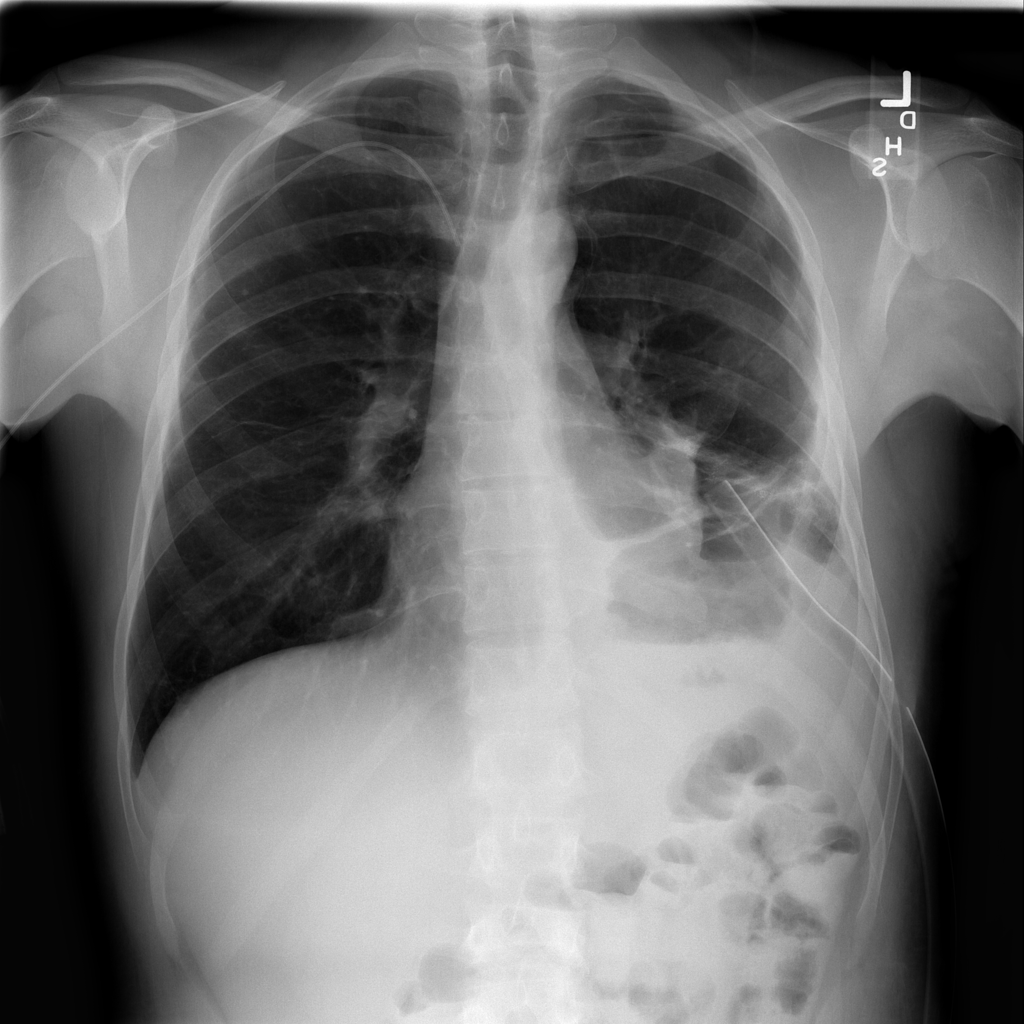

Showing up to 90 reference images for Pneumothorax.

PAT-3209 · IMG-000Pneumothorax

PAT-3209 · IMG-000

PA